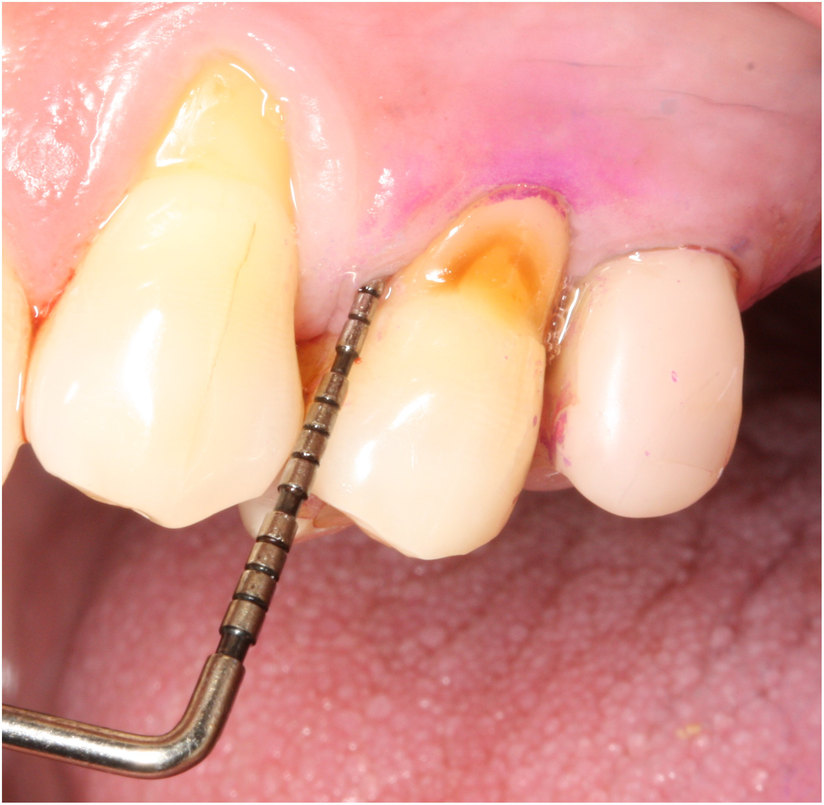

Présentation clinique : Récession vestibulaire de 3 mm dépassant légèrement la ligne muco-gingivale, sans perte osseuse interdentaire. Septa préservés. Les papilles sont intactes. L’examen révèle un brossage horizontal vigoureux avec une brosse à poils médium. Absence d’inflammation clinique. Classification de Miller : classe II.

Présentation clinique : Récession de 5 mm dépassant nettement la ligne muco-gingivale, avec perte osseuse interdentaire modérée. Papille mésiale absente. Classification de Miller : classe III. Tissu kératinisé résiduel : 1 mm. Présence de cément radiculaire exposé avec dépôts de tartre.